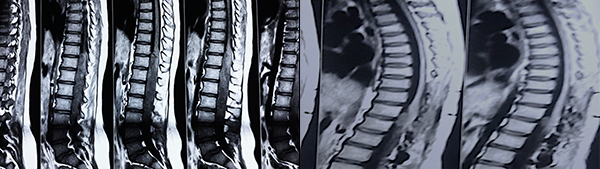

Se registraron dos reoperaciones ( casos 3 y 5 ). En el Caso 5 el paciente experimentó un empiema en el lecho quirúrgico y requirió retiro de la laminoplastía, lavado del foco infeccioso y tratamiento antibiótico por tres semanas, este paciente con Grado 3 en la escala de McCormick se mantuvo con Grado V de la misma escala de manera irreversible luego de un año de la cirugía. El caso 3 se trató de un tumor del cono medular diagnosticado inicialmente como Ependimoma Mixopapilar de la Cola de Caballo (Grado I OMS) en el que observó un residuo sobre la cara anterior medular en una IRM de control (Figuras 1 y 2). La reexploración evidenció la ubicación intramedular de la lesión y la revisión anatomopatológica definitiva concluyó que se trataba de un Ependimoma (Grado II OMS).

Figura 1: Caso 3. Ependimoma Dorsolumbar. Residuo cara anterior

Es evidente que el límite entre el tejido medular y tumoral en las lesiones como los astrocitomas es indiscernible lo que dificulta la posibilidad de resección completa; en los tumores como los ependimomas esta diferencia es más franca y permite seguir un plano de disección seguro (Figuras 3, 4 y 5). Lo anterior condiciona nuestros resultados como han puntualizado diversos autores.5,8 El estado general previo a la cirugía requiere de una valoración juiciosa de las posibilidades de resección. Por ejemplo, el caso 12 (Figura 6) es una paciente portadora de Enfermedad de Von Hippel Lindau, Hemangioblastoma cervical biopsiado en otra institución del exterior del país, fijación de columna cervical y sindrome de Cushing por exceso de medicación corticoidea cuya cirugía debió suspenderse en dos oportunidades por la disminución de su capacidad ventilatoria. Con estos antecedentes y la delgada capa de tejido medular evidenciada intraoperatoriamente se optó por una resección subtotal. A los cuatro meses de la cirugía la paciente recuperó la marcha autónoma y demás parámetros clínicos.

Figura 3: Caso 10. Ependimoma cervical pre operatoria: Lesión sólida C3 y dilatación siringomiélica. Posoperatorio: resección completa, disminución de la cavidad. Restos hemáticos decantados.